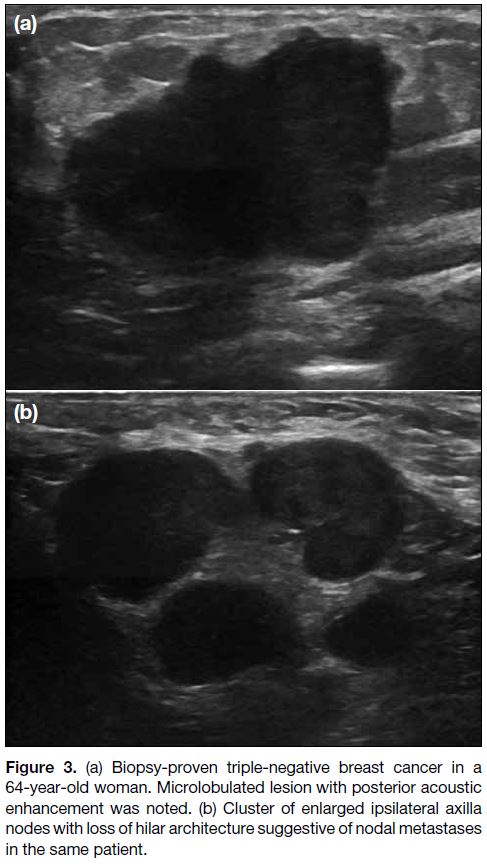

spiculated.[8] There was a significantly higher incidence of

microlobulated margins (40% vs. 9.6%) [Figures 2 3 4],

and significantly lower incidence of indistinct (26% vs.

42.3 %) and angular margins (26% vs. 42.3%) in TNBC

group compared with non-TNBC group (p = 0.006).

Figure 3. (a) Biopsy-proven triple-negative breast cancer in a

64-year-old woman. Microlobulated lesion with posterior acoustic

enhancement was noted. (b) Cluster of enlarged ipsilateral axilla

nodes with loss of hilar architecture suggestive of nodal metastases

in the same patient.

of microlobulated margins was highest (Figures 2 3 4).